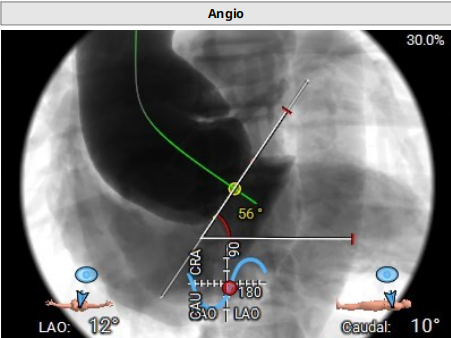

主动脉瓣环夹角56°:

术中造影角度LAO 13°,CAU 11°;主动脉弓、降主动脉及双侧髂总动脉散在钙化,主动脉弓、腹主动脉局部管壁增厚,腹主动脉局部管壁不规则;升主动脉夹层、窦管交界增宽。